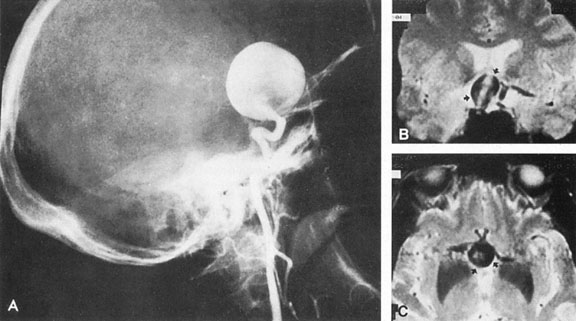

Fig. 7. Supratentorial arteriovenous malformation in a 28-year-old woman with a history of focal motor seizures for many years and a recent subarachnoid hemorrhage. A: Lateral projection carotid arteriogram demonstrating a huge deep hemispheral arteriovenous malformation. B: Frontal projection. C: Fundus photograph showing anomalous tortuous vasculature in each eye. No retinal arteriovenous shunt was detectable.

Fig. 8. Multiple supratentorial arteriovenous malformations (AVMs). A: Lateral projection of left carotid arteriogram shows dilated afferent artery (solid arrow) feeding the right hemispheric parietal AVM (open arrow). B: Right carotid injection fills a second, more posteriorly located, parietooccipital AVM (open arrow), which drains immediately to markedly dilated cortical veins (curved arrow).

Fig. 9. Carotid arteriogram of an occipital lobe arteriovenous malformation (AVM). Lateral (A) and frontal (B) projections demonstrating a small occipital AVM (arrow). The patient was a 23-year-old woman who presented with severe apoplectic unilateral headache, total left homonymous hemianopia, and mild nuchal rigidity. Despite xanthochromic cerebrospinal fluid, she was initially diagnosed elsewhere as having migraine. An AVM was successfully resected, and a small occipital lobe hematoma was removed.